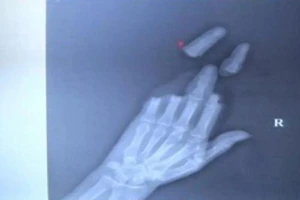

Người đàn ông mất 3 ngón tay vì thả diều